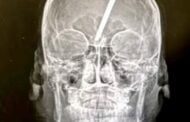

Imbasan CT menunjukkan tempuling itu menembusi tengkorak jauh ke dalam otak mangsa. BANGKOK: Seorang remaja berusia 14 tahun di Thailand bernasib baik terlepas daripada maut selepas tempulin... Read more